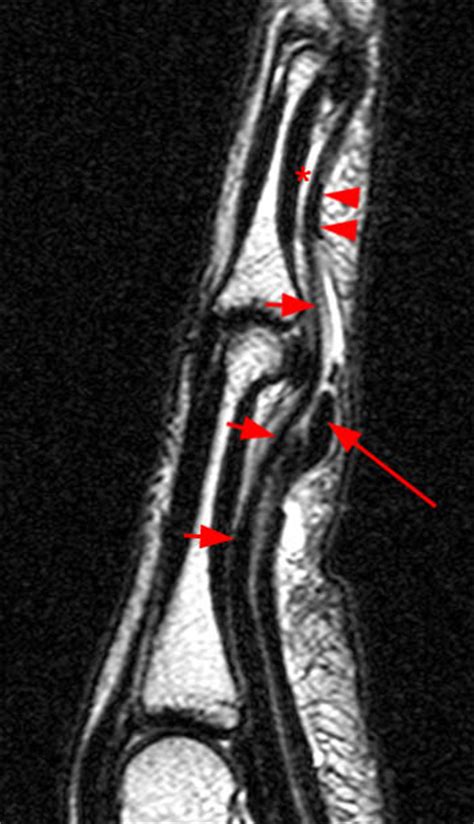

Pulley Lesion Of The Fingers - Radsource

Pulley Lesion of the Fingers - Radsource radsource.us

pulley flexor radsource mri pulleys tendon system fingers lesion annular anatomy cruciate 2005 clinic web volar december

flexor tendon radsource mri fdp